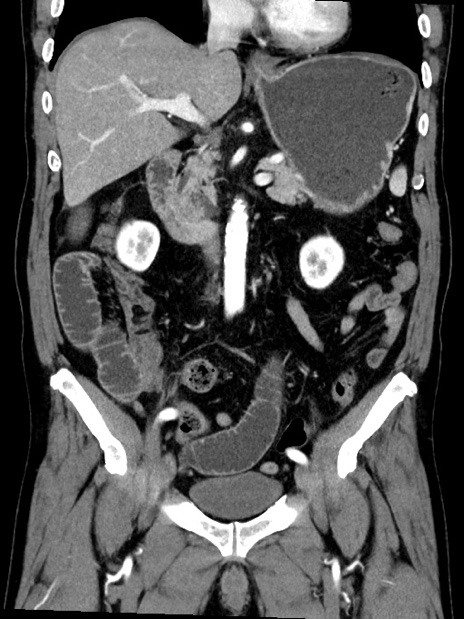

症例35(冠状断像)

【症例】70歳代 男性

【主訴】腹部膨満、嘔吐

【現病歴】昨日より腹部膨満感出現。本日増悪し、仙痛出現。嘔吐あり、受診。

【既往歴】糖尿病、胆摘後

【身体所見】BP 149/80mmHg、HR 74/min、BT 35.9℃、腹部:膨満、軟、圧痛なし。腸雑音減弱あり。上腹部正中切開瘢痕あり。

【データ】WBC 13500、CRP 1.72